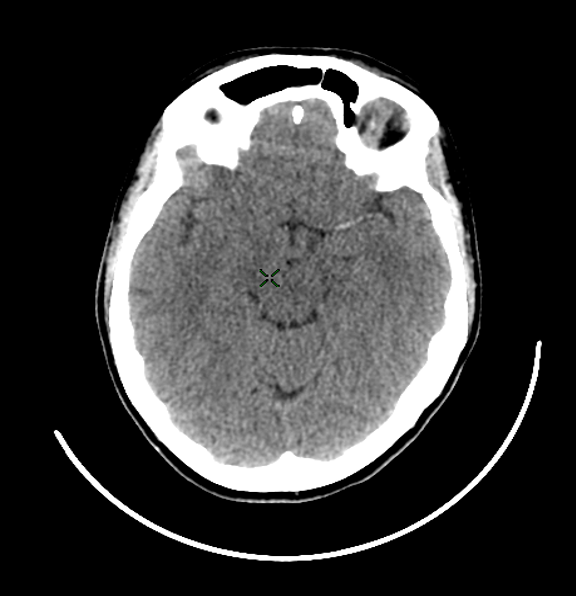

What type of stroke is shown

Ischaemic stroke